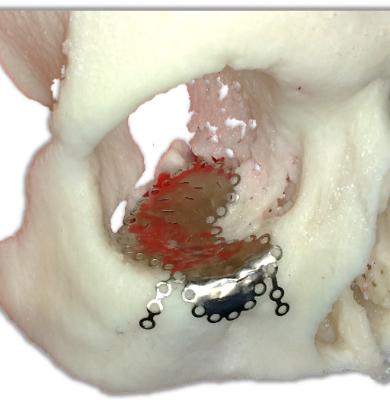

Индивидуальный имплант для реконструкции глазной орбитыИндивидуальные импланты для реконструкции костных структур глазной орбиты

Индивидуальные силиконовые эктопротезы на титановых удерживающих имплантах